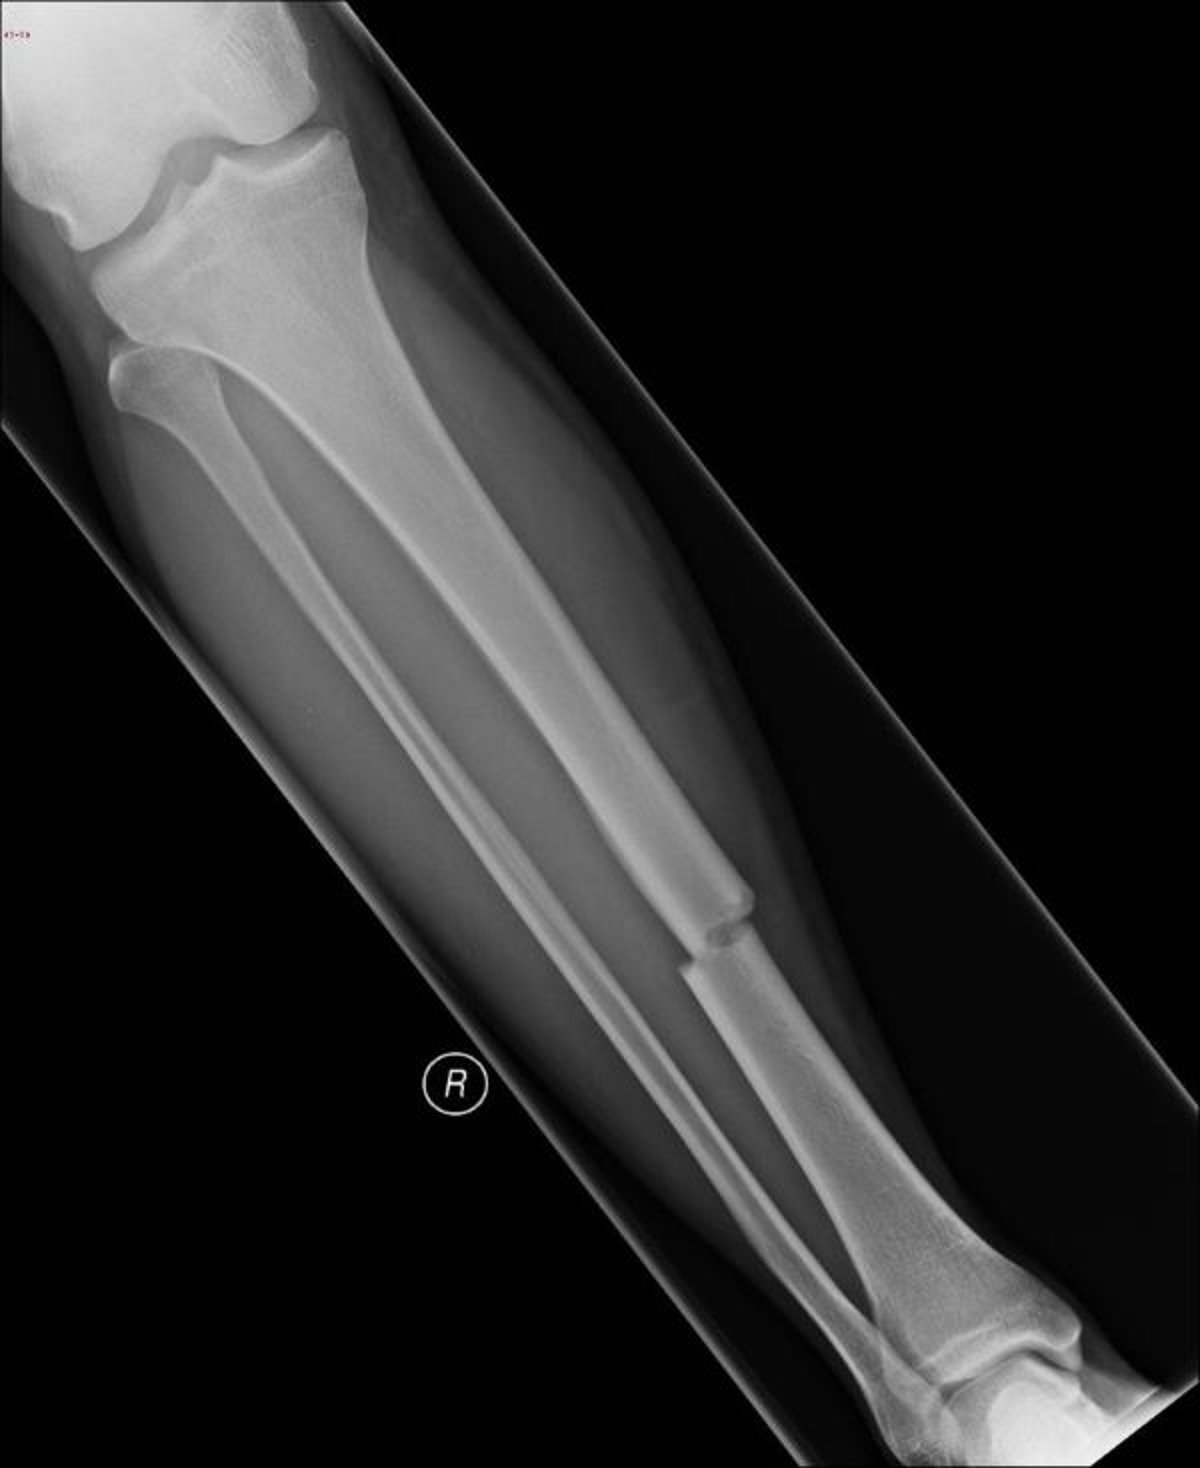

عظم الظنبوب المكسور

تُظهر هذه الصورة الشعاعية وجود كسر في منتصف عظم الظنبوب.